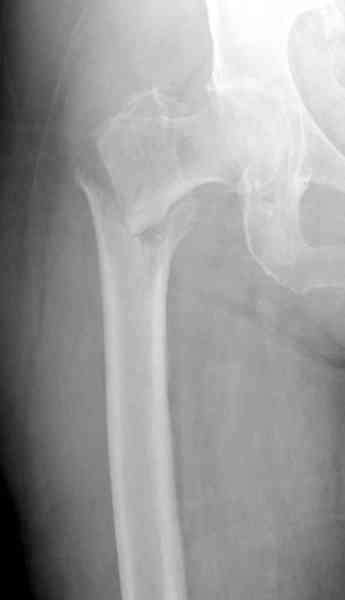

Здесь сканнированные снимки импланта и операционные снимки больной.